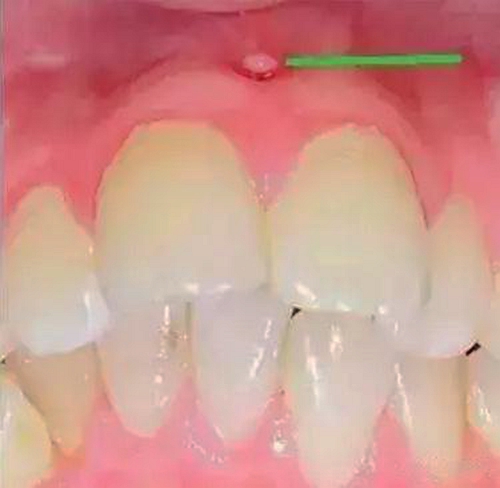

第五步:急性根尖周炎

當您臉腫得睜不開眼睛時,您撐著眼睛說:“沒什么大不了的,吃吃消炎藥就好了。”

牙醫(yī)卻著急地說:“牙齒急性根尖周炎感染可能引起間隙感染,嚴重的會危及生命。此時,需要到正規(guī)口腔醫(yī)院治療患牙,配合藥物治療,必要時做膿腫切開引流術(shù)。”